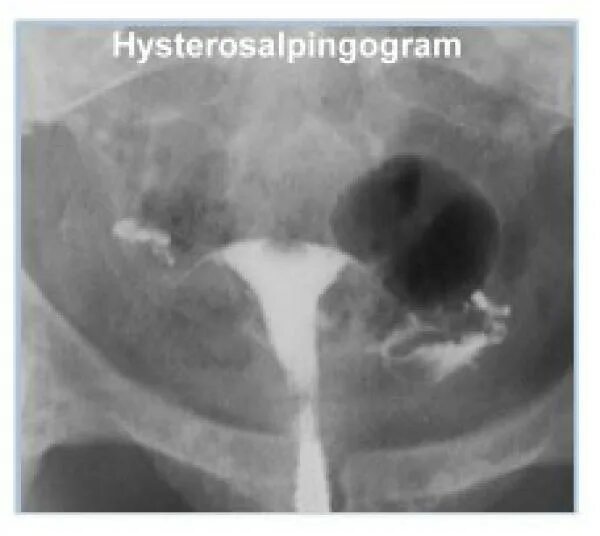

Проходимость маточных труб форум